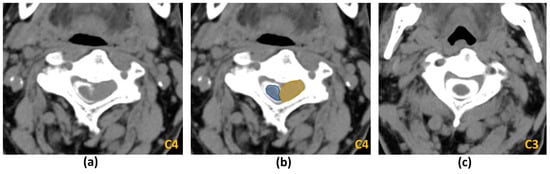

4.1. Pre-Treatment Planning

5. Deep Learning (DL) in MSCC Imaging